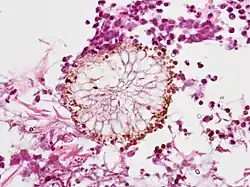

| Diagnostic method | Microscopic exam of affected tissue[3] |

Trichosporonosis is a systemic disease associated with fungi in the genus Trichosporon.It can occur in people who are immunosuppressed.[5]Trichosporon asahii is the predominant cause of Trichosporonosis, especially invasive forms of the infection. While other Trichosporon species can cause infections, T. asahii accounts for the majority of clinical cases and is considered the most pathogenic and lethal species within the genus[4]

Trichosporon is a genus of anamorphic fungi in the family Trichosporonaceae. All species of Trichosporon are yeasts with no known teleomorphs. Most are typically isolated from soil, but several species occur as a natural part of the skin microbiota of humans and other animals.Trichosporon asahii is a non-Candida yeast that has been reported to cause infections in immunocompromised patients. T. asahii is the most prominent human pathogen in its genus, causing more than half of all Trichosporon infections[4][7][8]